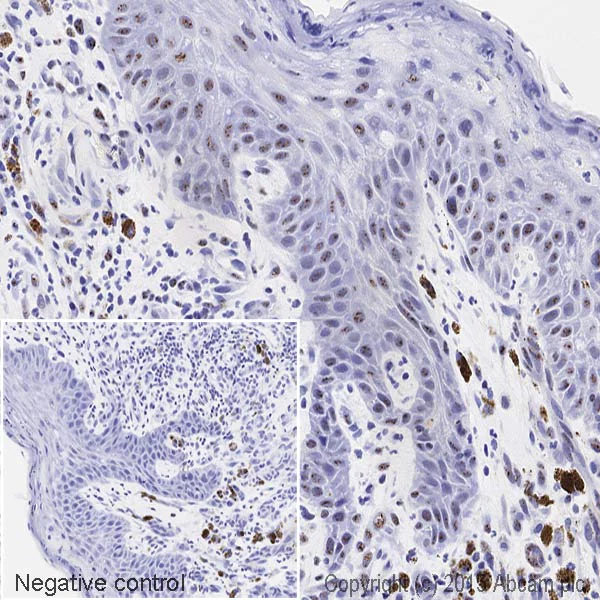

Immunohistochemistry (Formalin/PFA-fixed paraffin-embedded sections) - HRP Anti-SF3a66 antibody [4G8] (AB201747)

IHC image of SF3a66 staining in a section of formalin-fixed paraffin-embedded human normal skin*, performed on a Leica BOND. The section was pre-treated using heat mediated antigen retrieval with sodium citrate buffer (pH6, epitope retrieval solution 1) for 20mins. The section was then incubated with ab201747, 1/100 dilution, for 15 mins at room temperature. DAB was used as the chromogen. The section was then counterstained with haematoxylin and mounted with DPX. The inset negative control image is taken from an identical assay without primary antibody.

For other IHC staining systems (automated and non-automated) customers should optimize variable parameters such as antigen retrieval conditions, primary antibody concentration and antibody incubation times.

*Tissue obtained from the Human Research Tissue Bank, supported by the NIHR Cambridge Biomedical Research Centre.